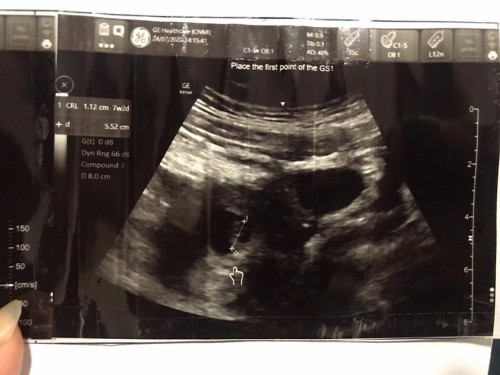

แม่ๆท่านไหน เป็นแบบเราบ้างคะ เจอลูกน้อยแล้วได้ยินเสียงหัวใจเต้นปกติ แต่มี #ภาวะแท้งคุกคาม เนื่องจากเราปวดท้องน้อยแต่มีเลือดออกนิดเดียวแบบติดกางเกงน้อยมาก คุณหมอแจ้งว่าขาดฮอรโมน ตอนนี้คุณหมอให้ยากันแท้งมาทานแล้วค่ะ #แอบกังวน ตอนเจอลูกน้อยน้ำตาคลอเบ้าเลยค่ะ พอออกจากห้องตรวจเจอสามีคือร้องไห้โฮเลย เป็นห่วงลูกน้อยมากค่ะ #ขอบคุณสำหรับคำตอบล่วงหน้านะคะแม่ๆ